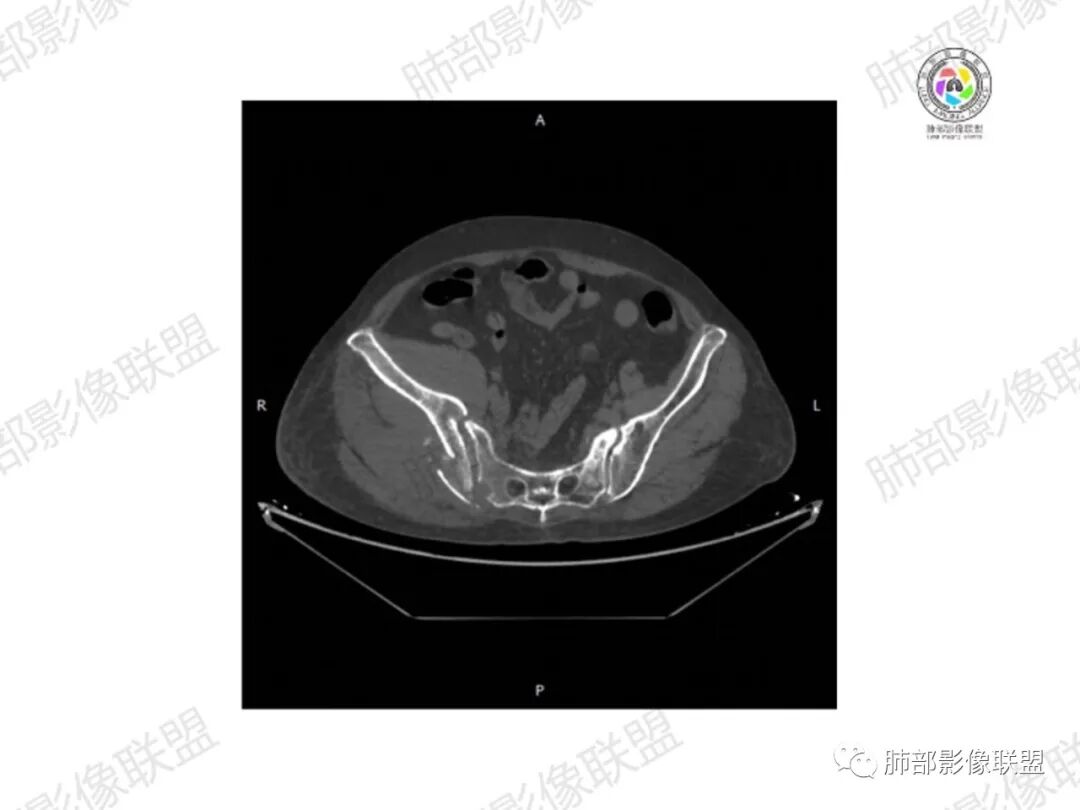

2.右髂骨轻度变形伴广泛骨质吸收破坏,边界不清且突破骨皮质。近中线区以溶骨性破坏为主,髂骨翼一侧则成骨性改变明显,骨表面见垂直骨针或花边样高密度瘤骨。

3.患骨多处皮质断裂,符合病理性骨折。注意折端可能会形成骨痂,但本例无论是形态还是部位都不符合骨痂。

4.患骨两旁(即盆骨内外)见边界不清的较大范围软组织快影,其间偶见骨化影。

1.边界不清的骨质吸收破坏,溶骨明显,骨皮质突破,软组织肿块,种种迹象表明其恶性无疑!

2.但注意这是有“成骨”的恶性骨肿瘤!我们知道老年患者的骨原发性恶性肿瘤“成骨”非常少见。少数转移瘤可为成骨型或混合型,女性患者如乳腺癌骨转移等。在男性,最典型的成骨转移是前列腺癌。

本例右侧髂骨具有较为典型的“骨肉瘤”影像学特征,有边界不清的吸收破坏、有新生骨、形成软组织肿块等等。

4.“成骨肉瘤”绝大多数发生于青少年,发生于老年患者则往往见于其他因素,如诱发于畸形性骨炎(Paget病,本例影像不支持),骨照射、骨坏死等。其他如骨旁骨肉瘤等,发病年龄可以偏大。

本例非常具有临床意义,值得我们警惕!